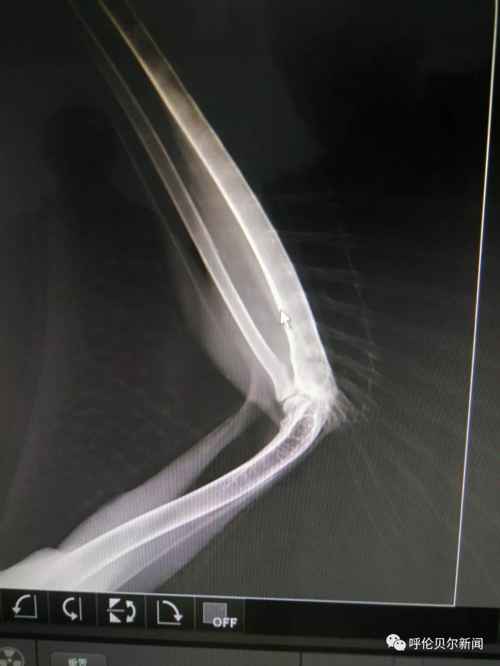

双龙还给雕鸮换了一处居所,在镇区东部新村的大仓库内,“这仓库里有房架子,雕鸮可以飞到高处休息,像在林子里一样。“这家伙很聪明,第一次在大房子里飞的时候撞在窗玻璃上,第二次它就能够稳稳地站在窗台上了。”双龙夸讲雕鸮时的表情像在夸讲自己的孩子。 >>>2019年3月15日 雕鸮活动在人迹罕到的偏僻之地,通常远离人群,属于夜行性猛禽,以各种鼠类为主要食物,被誉为“捕鼠专家”,也吃兔类、蛙、刺猬、昆虫、雉鸡和其他鸟类。然而,被救的这只雕鸮却在过去的203天里,与人类亲密接触。双龙的蒙语,许是它神经条件反射的反射弧,许是它渐渐感受到的源自人类的善意。3月15日上午,双龙带着雕鸮到新右旗人民医院拍了放飞前的最后一张X光片,无需挂号,一路绿色通道。医生告诉双龙骨头断裂处已长出骨甲,恢复得特别好。“你看,你看,这是你的翅膀,你痊愈啦,就该回 家了!”在医院的电脑前,双龙仍然用哝哝软软的蒙语与雕鸮沟通……